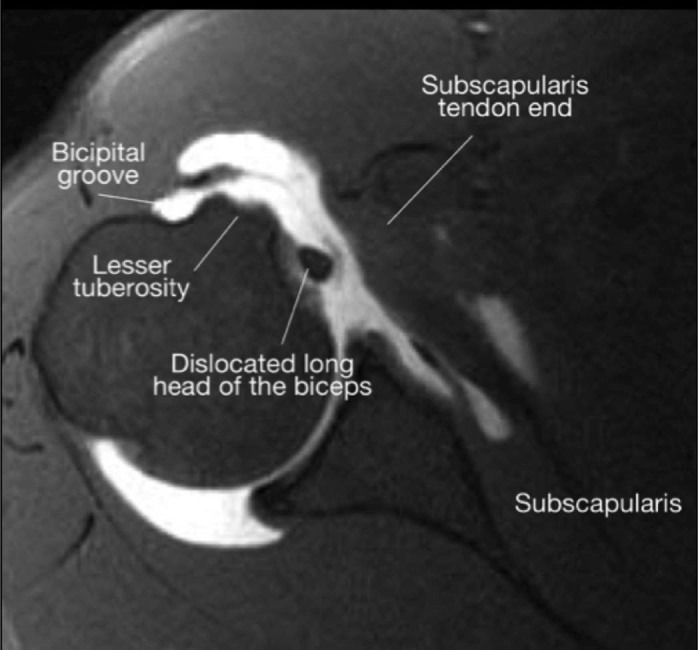

Adams et al also described a systematic approach of diagnosing subscapularis tears on preoperative MRI. Their 4-step eval‎uation consists of (1) the presence or absence of a subscapularis tear on axial cuts, (2) subluxation of the long head of the biceps tendon on axial cuts, (3) subscapularis atrophy on sagittal images, and (4) subscapularis tear off of the lesser tuberosity on sagittal images (Fig. 2). Subscapularis pathologic change on 2 of 4 images was considered to indicate subscapularis tearing. With this approach, they reported 73% sensitivity and 94% specificity for correct diagnosis of a subscapularis tear.1 There was an increase in diagnosis with larger tears that involved >50% of the tendon in the cephalad-caudal direction, which is in agreement with previously reported studies.3

Figure 2.

Open in a new tab

Applying the 4-step magnetic resonance imaging eval‎uation by Adams et al.1 (A) Axial image showing the biceps tendon in the groove with an obvious retracted tear of the subscapularis tendon. (B) Sagittal image showing grade 2 fatty infiltration of the subscapularis muscle. (C) Sagittal image showing a bare lesser tuberosity.